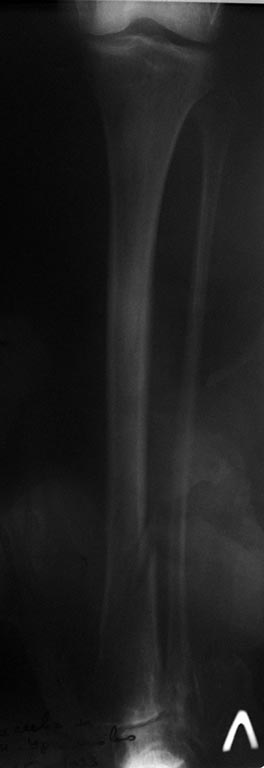

Пациентки 65 лет, получила травму 05.03.2015 г., упала на улице. В

анамнезе, примерно 20 лет назад был "перелом внутренней и наружной

лодыжки левой голени", лечилось консервативно.

Вопрос, забивать антеградно БИОС или же Артодезирование штифтом?